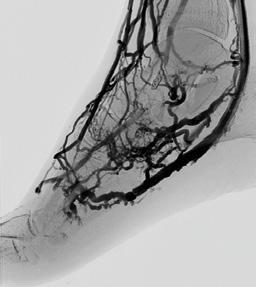

Ons lichaam beschikt over bloedvaten die zuurstof en voedingsstoffen naar onze organen en ledematen brengen. Bij kritieke ledemaatischemie zijn de bloedvaten in het been — vooral de slagaders — zo zwaar aangetast door aderverkalking dat er nauwelijks nog zuurstofrijk bloed in de voet komt (Figuur 1). Dat veroorzaakt pijn in rust of ‘s nachts en wondjes die niet genezen. Zonder behandeling ontstaat weefselversterf (gangreen), met een verhoogd risico op infectie, amputatie en overlijden.

Bij de meeste patiënten kunnen we de doorstroming verbeteren. Afhankelijk van de ernst en de locatie van deze verstoppingen kiezen we voor een ballondilatatie (Percutane Transluminale Angioplastiek of PTA) of een overbruggingsoperatie (bypass) (Figuur 2a en b). Bij een kleine groep patiënten – vaak met diabetes en/of chronisch nierlijden – zijn de bloedvaten in het onderbeen en de allerkleinste vaatjes in de voet zo ernstig verstopt dat klassieke technieken geen haalbare optie zijn.

GEBLOKKEERDE SLAGADER

Bij diep veneuze arterialisatie (DVA) draaien we als het ware het systeem om. In plaats van het bloed via slagaders (arteries) naar de voet te brengen, leiden we het zuurstofrijke bloed rechtstreeks in de diepe aders (venen) van het onderbeen en de voet. Normaal brengen deze aders het bloed terug naar het hart, maar na deze ingreep kan zuurstofrijk bloed via dit netwerk naar de voet stromen en zo de weefsels opnieuw voeden. Het doel? Wondgenezing stimuleren en amputaties vermijden, zelfs als er geen arteriële doorgangen meer beschikbaar zijn.

Diep veneuze arterialisatie is geen standaardbehandeling, maar een laatste redmiddel voor patiënten waarbij alle klassieke opties zijn uitgeput. Door middel van deze ingreep proberen we een amputatie van het onder- of bovenbeen te vermijden. Voor de procedure onderga je een grondig preoperatief onderzoek om te bepalen of veneuze arterialisatie geschikt is voor jouw specifieke situatie.

De procedure vindt plaats in onze hybride operatiezaal onder algemene verdoving. Via kleine prikken in de lies en de voet worden een slagader en een diepe ader met elkaar verbonden — dit noemen we een arterioveneuze (AV) fistel. Vervolgens plaatsen we een stent die het bloed richting voet leidt (Figuur 4, voor en na).

Na deze eerste ingreep heeft het lichaam tijd nodig om zich aan te passen. Gedurende 6 à 8 weken volgt een rijpingsproces waarbij het aderlijk netwerk zich verder ontwikkelt en connecties maakt met het slagaderlijk netwerk (Figuur 5, voor en na). Tijdens deze periode doen we regelmatige controles middels echografie om te beoordelen of de nieuwe doorstroming goed functioneert. Meestal is nog een tweede ingreep nodig om kleine zijtakjes af te sluiten, zodat het bloed verder richting de voet kan worden gestuurd.

Nauwkeurige opvolging is dus cruciaal. We combineren medische beeldvorming met gespecialiseerde wondzorg. Vaak is een beperkte ingreep nodig om afgestorven

weefsel (bv. een teen of een deel van de voet) te verwijderen. Deze kleine amputatie wordt meestal pas uitgevoerd wanneer de bloedvoorziening voldoende hersteld is — ten vroegste 6 à 8 weken na de DVA.

Genezing van chronische voetwonden duurt vaak maanden, maar het belangrijkste is dat we bij ongeveer 60 tot 70% van de patiënten een amputatie van het onder- of bovenbeen kunnen voorkomen. DVA is geen ‘mirakeloplossing’, maar biedt wél hoop voor patiënten bij wie klassieke ballondilatatie/stent of bypass tot voor kort geen uitweg meer bood.